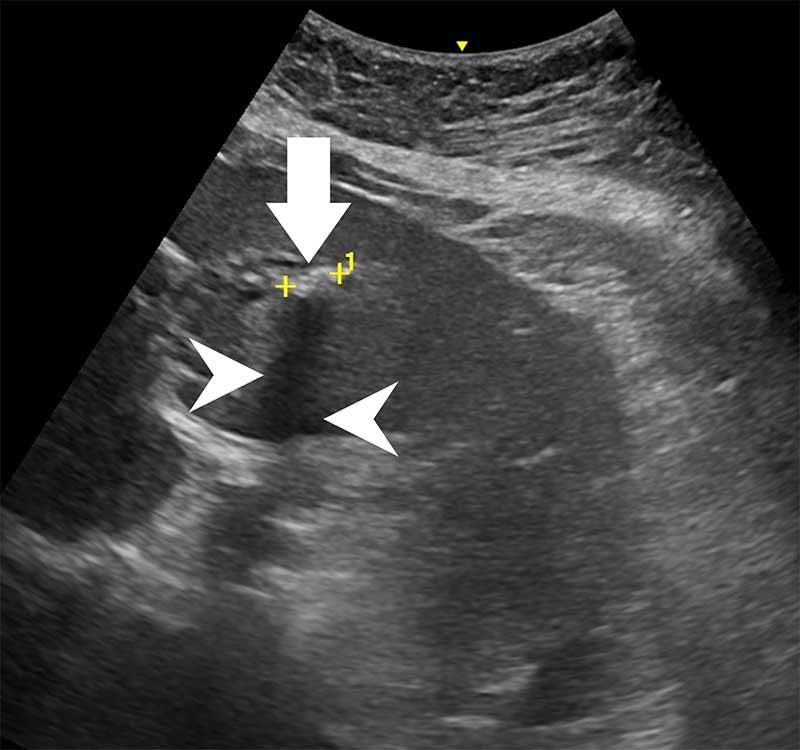

59歲陳女士長期承受間歇性腹痛,九月間於外院住院治療仍無改善,出院後轉至臺中市立老人復健綜合醫院。於肝膽腸胃科由內科部部長賴學洲醫師安排腹部超音波及核磁共振檢查,確診為左側肝內結石合併慢性肝內膽管炎及膽囊細沙併慢性膽囊炎,後經一般外科主任曹連誠醫師評估,安排 3D 立體內視鏡左肝切除加膽囊切除手術。患者術後恢復良好,第二天即可下床行走,自理生活,成功擺脫惱人的腹痛與長年不適。

肝臟及膽道手術過去大多以開腹方式進行,術後疼痛及恢復期長。此次採用的3D 立體內視鏡技術可清晰呈現肝臟內細微結構,3D立體視角搭配螢光血流影像,即時辨識血管與膽管位置,提高手術安全性與精準度。15 公分大的肝臟組織,僅透過約 5 公分傷口取出,可大幅降低術後疼痛與感染風險,縮短住院及復原時間,保留最多肝臟功能,同時避免肝內膽管癌長期風險。